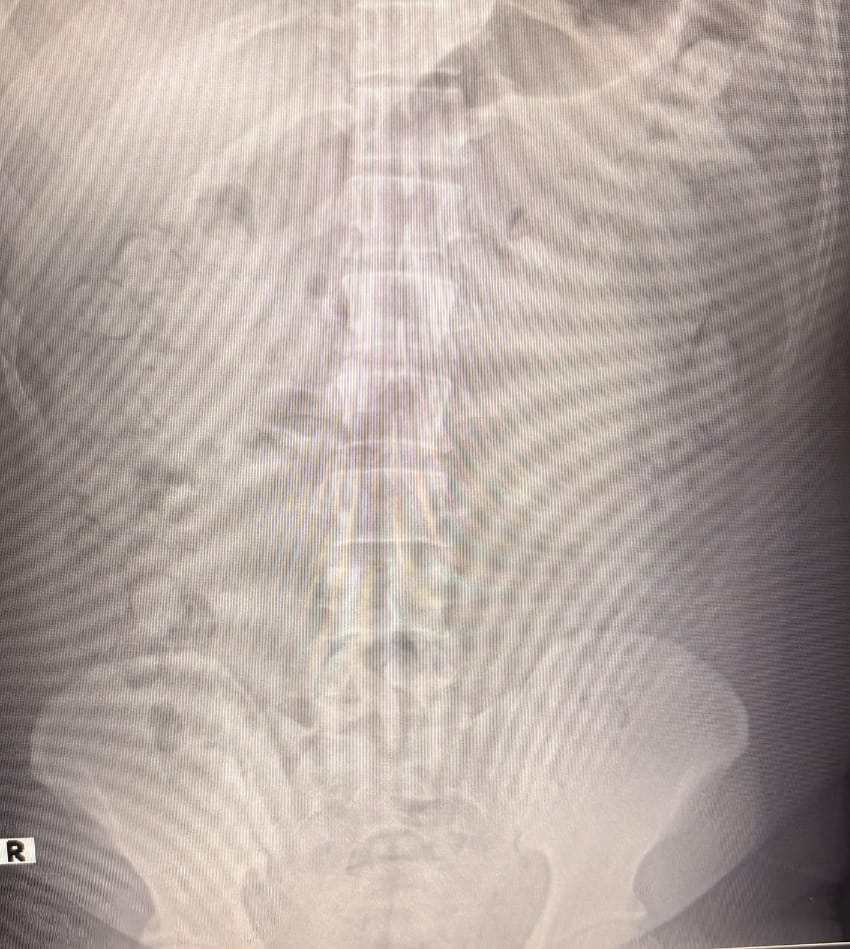

Röntgen Filmleri Gerçeği Ortaya Çıkardı

Uyuşturucunun paketlenme şekli ekiplerin dikkatini çekti. Şahıslar hastaneye sevk edilerek detaylı kontrollerden geçirildi. Röntgen sonuçlarında, şüphelilerin mide ve bağırsaklarında çok sayıda kapsül olduğu tespit edildi.

Kontrollü tıbbi müdahalenin ardından, toplam 140 kapsül metamfetamin çıkarıldı.